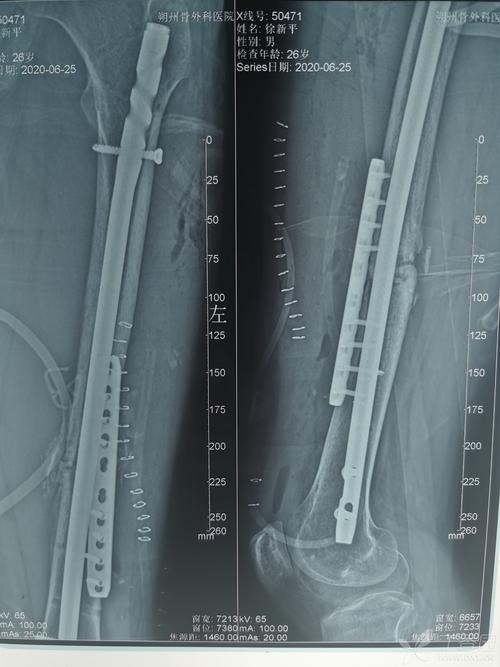

股骨干骨折愈合好图片,股骨颈骨折术后6不要

看这例股骨干骨折术后接下来将如何处理?

股骨干骨折

写美篇 第一例患者为42岁女性,体态偏胖,右股骨干中下段骨折,九个月前

股骨干骨折不愈合次置骨换钉十钢板固定

股骨干骨折术后感染不愈合

股骨干骨折髓内钉图片